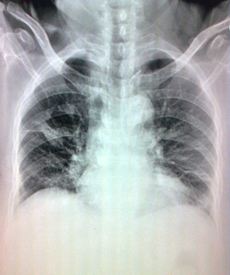

摘要:间质性肺病(interstitial lung disease,ILD)呈现出了较高的发病率和病死率,ILD和肺癌(lung cancer,LC)之间的联系早年就已经被发现,间质性肺病与肺癌的联系近年来逐渐引起重视,多项研究已证实某些特殊类型的ILD罹患肺癌的风险高于一般人群。本文将主要针对ILD合并肺癌相关的临床研究进展作一综述。

2 ILD-LC流行病学

IPF和其他ILD中LC发病率。国外一项回顾性研究,涉及103名IPF患者,报告了20.5%的患者在平均52-44.8个月的随访中出现LC。在一项涉及205名隐源性纤维化肺泡炎患者的研究中,LC发生率在4年随访中为9.8%。一项日本研究分析肺纤维化合并肺气肿人群,LC发病率在3年随访中为46.8%(22/47),在法国肺抱子菌研究记录的10年随访中为14.6%,其他特发性ILD,如非特异性间质性肺炎、脱皮间质性肺炎、呼吸性毛细支气管炎相关间质性肺病和淋巴细胞间质性肺炎的数据则很少[2]

3辅助检查和诊断

3.1 CT扫描和PET-CT。

LC大多是在ILD之后才被诊断,最近的一个研究比较了104名ILD-LC患者和1160名LC患者,显示前者有更高比例的胸膜侵犯。ILD中,LCs主要表现为周围肿瘤(503名患者中的83.9%),在纤维变性区域内/附近(474名患者中的68.1%),在下肺叶(2877名患者中的58.7%)。在66例外周T1N0肺癌中,其中64%发生在下叶,53%发生在纤维化/健康组织界面,31.8%发生在纤维化区域。大多数肿瘤由实体、圆形或椭圆形病变组成,中位倍增时间为77天。LC-ILD患者的纵膈分析更加困难,因为在55-93%的ILD病例中,纵膈淋巴结呈反应性增大。CT纵膈分期的特异性在IPF患者中降低(47%对84%)。PET-CT在有或没有ILD的LC患者中显示出相似的敏感性和特异性。比较LC-IPF患者和没有ILD的LC患者,研究证明使用PET-CT和单独使用CT相比,将诊断准确率从14%提高到33%。